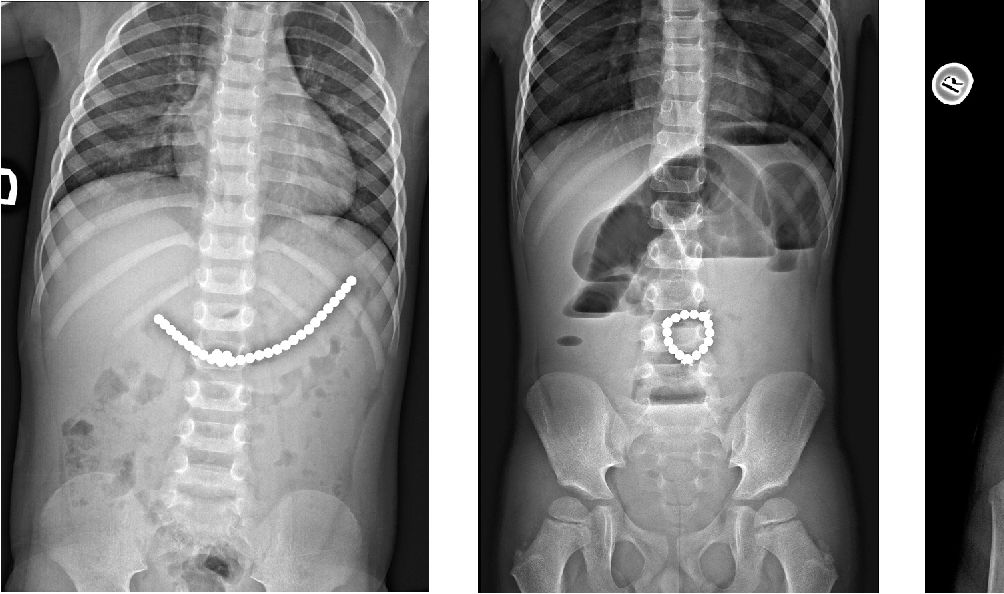

Magnesy widoczne na prześwietleniu

Magnesy widoczne na prześwietleniu © "Multiple magnet ingestion in children"